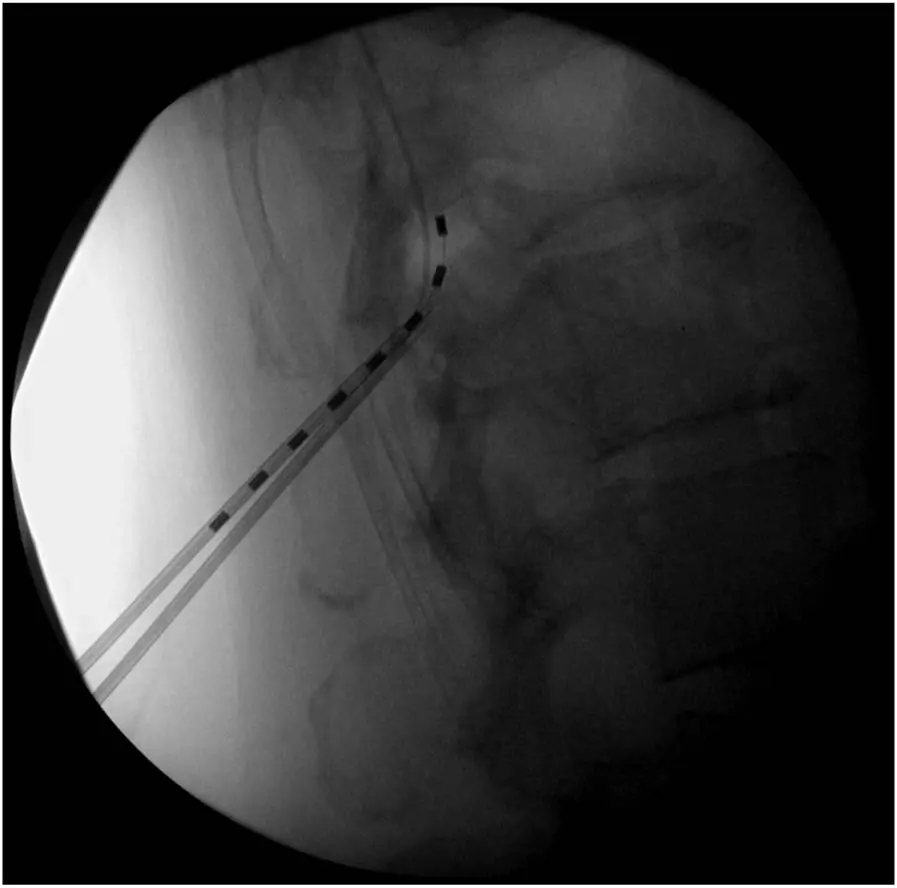

②试验期

对于初步评估符合条件的患者,通常会先进入一个试验期。在这个阶段,医生会采用临时电极进行植入,植入过程一般在局部麻醉下进行。在试验期间,患者需要密切关注自身的感受,记录在不同刺激参数下疼痛的变化情况、是否出现异常感觉以及身体功能的改善程度等。试验期通常持续 5 - 7 天,通过这段时间的观察,医生可以根据患者的反馈初步判断脊髓电刺激对该患者是否有效,以及确定最适合患者的刺激参数。